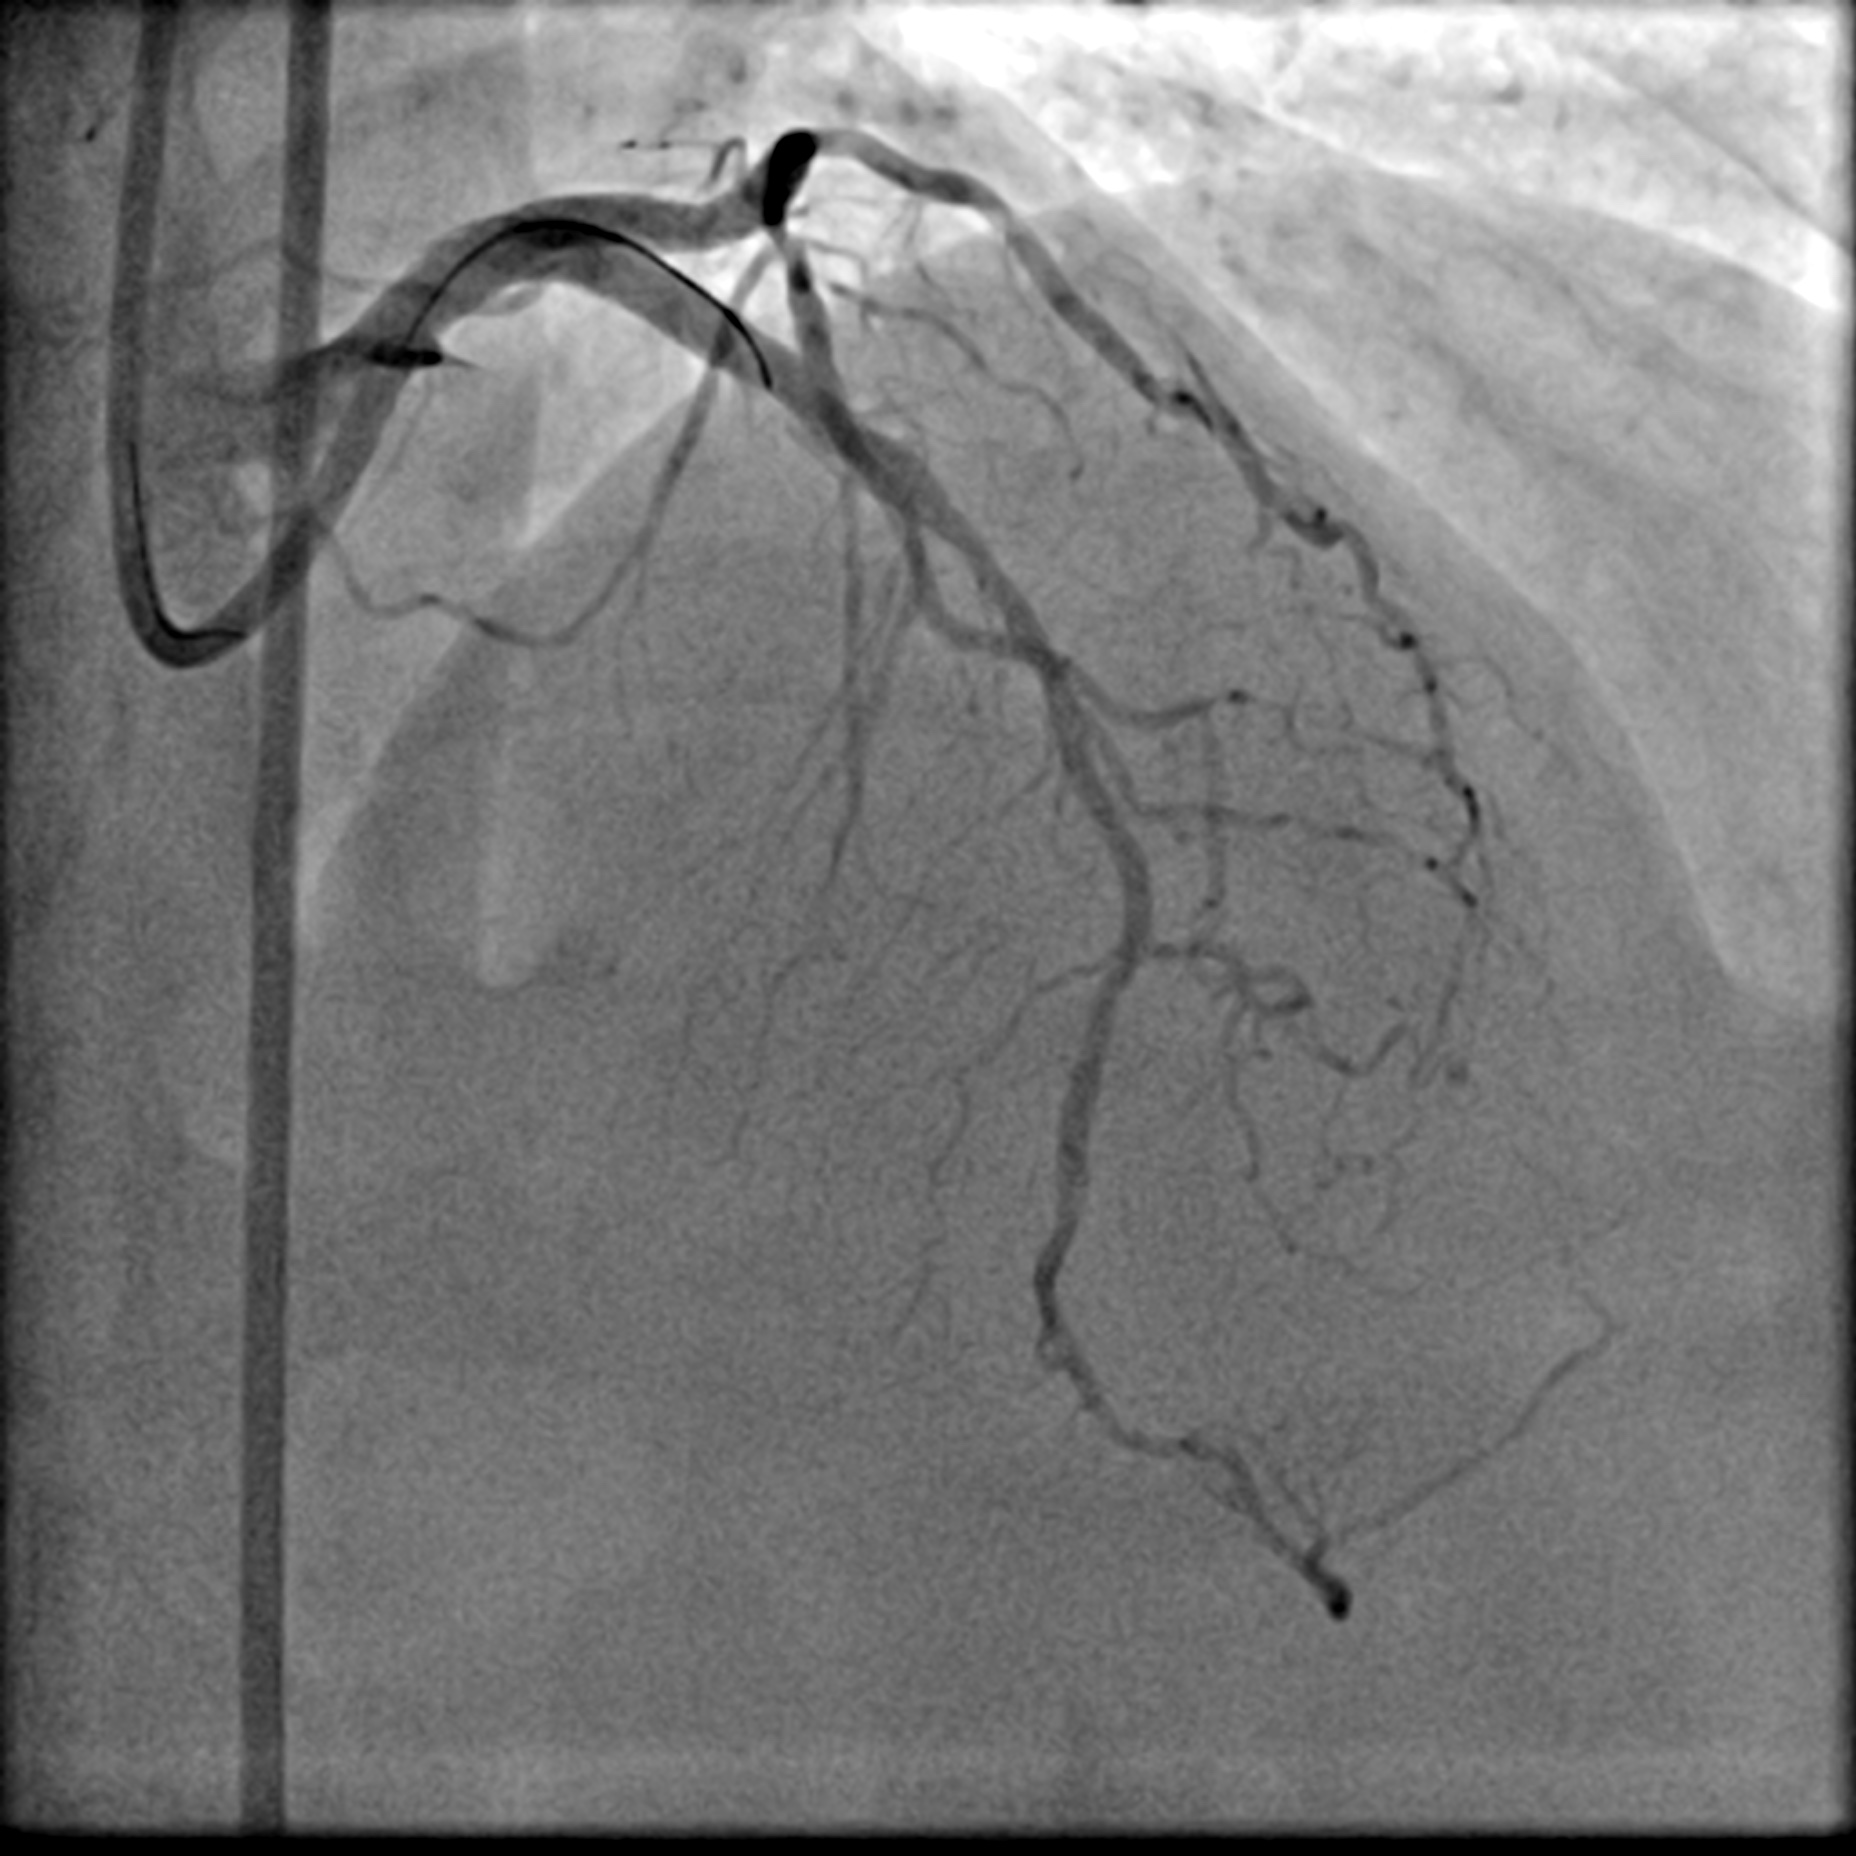

A LMS hybrid therapy was planned. A 7 Fr EBU 3.5 catheter was engaged to the LMS. Two workhorse wires were placed in the distal LAD and LCx. The LAD was pre-dilated with a 3.5 mm cutting balloon without facing significant difficulty. However, pre-dilatation of the LCx with a 3.5 mm cutting balloon was unsatisfactory due to the calcium nodule. This was overcome with lesion preparation using a 3.5 mm Lithix balloon. Adequate lesion preparation was confirmed with repeated angiography and IVUS assessment. The ostial LCx was treated with a 3.5 x 20 mm Drug-Coated Balloon (DCB), while the LMS-LAD segment was stented with a 4.0 x 22 mm Drug-Eluting Stent (DES). Proximal Optimization Technique (POT) was performed using a 4.5 mm NC balloon, and the stent in the LAD segment was post-dilated with a 4.0 mm NC balloon. Repeated angiography revealed a Type B dissection with a narrowed lumen in the LCx, necessitating stenting. The LCx was re-wired using a dual-lumen catheter from the inner frame of the LMS stent. The stent strut was opened with a 2.0 mm balloon and a 3.5 mm NC balloon. T-stenting of the ostial LCx was performed with a 3.0 x 26 mm DES, utilizing a balloon catheter in the LAD wire as a marker. The LCx stent was first post-dilated with a 3.5 mm NC balloon. Subsequently, the Kissing Balloon Technique (KBT) was performed with a 4.0 mm NC balloon in the LAD and a 3.5 mm NC balloon in the LCx. Finally, repeated POT was completed with a 4.5 mm NC balloon in the LMS.

Dissected LCx.mp4

LCA final AP cran.mp4

LCA final AP Caud.mp4